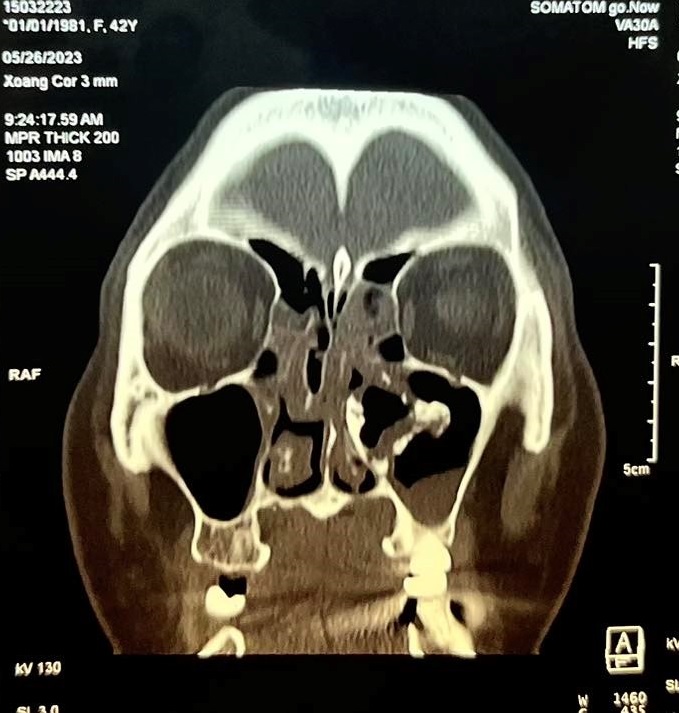

Bệnh nhân nữ, 42 tuổi, không có tiền căn chấn thương vùng hàm mặt trước đó, là công nhân của công ty may mặc, bệnh nhân luôn có cảm giác nghẹt mũi trái, cảm giác dịch nhầy chảy từ mũi xuống họng nhưng không khạc ra được, các cảm giác nhức vùng mặt cùng bên ngày càng rõ nên bệnh nhân đã đi khám nhiều nơi điều trị nhưng bệnh vẫn không thuyên giảmGần đây bệnh nhân xuất hiện thêm đau nhức vùng mắt trái cùng bên nên đã đến khám tại Bệnh viện Quận 4. Qua nội soi thăm khám và thực hiện chụp CT-Scan phát hiện bệnh nhân có cấu trúc mật độ giống xương dính vào thành trong xoang hàm bên trái, đẩy lệch vách mũi xoang về phía vách ngăn gây hẹp hốc mũi bên trái kèm viêm xoang hàm sàng 2 bên và concha bullosa cuốn mũi giữa bên phải gây tắc nghẽn đường dẫn lưu của xoang hàm bên phải

Hình ảnh CT scans mũi xoang